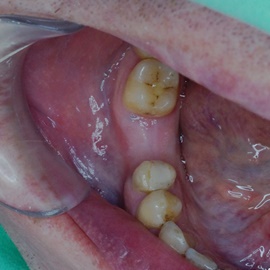

Przedtrzonowce często należą do okolicy estetycznej należy więc zwrócić wzmożona uwagę na poprawną anatomię tkanek kości i dziąsła. Po utracie zęba 25 pacjentka kilka lat chodziła bez jego uzupełnienia, doszło do przesunięcia się zęba 26. U tej pacjentki przed laty był wykonany most jednobrzeżny na czwórce, dość szybko doszło jednak do przeciążenia zęba filarowego, zaniku kości wyrostka i wreszcie pęknięcia korzenia zęba filarowego mostu. Po ekstrakcji i wygojeniu kości stwierdzono ubytek kości wyrostka przekraczający objętość 50% stanu początkowego. Stąd główny nacisk położono na odbudowę tkanek. Uzyskano zadowalający wynik anatomiczny.